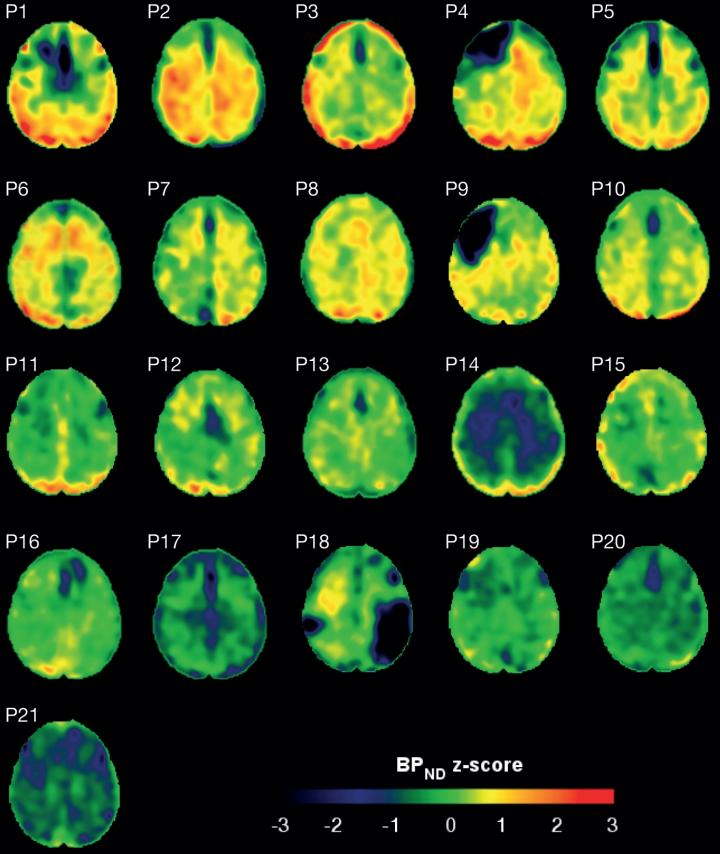

Brain Scan Images Showing Protein Tangles

image: These scans show the amount of tau protein in the brains of patients who have suffered a traumatic brain injury. Red represents increased tau accumulation. view more

The study used a type of brain scan, called a PET scan, combined with a substance that binds to tau protein, called flortaucipir, to study the amount of tau protein in the brains of head injury patients.

The results revealed that, collectively, patients with head injury were more likely to have tau tangles. The paper also showed that patients with tau tangles had higher levels of nerve damage, particular in the white matter of the brain. None of the healthy individuals had tau tangles.